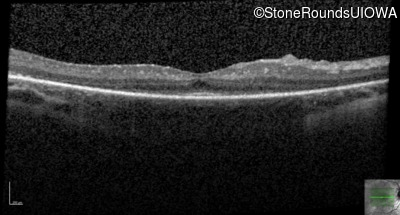

Optical Coherence Tomography - Left - 20/50 -1

Exemplar / OCT Stack